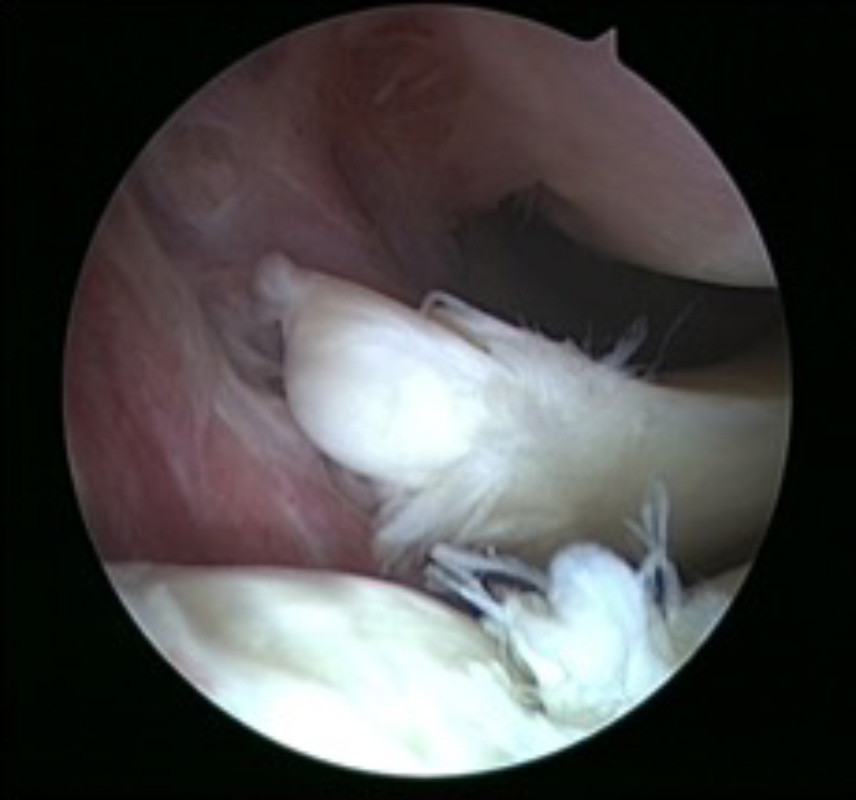

Insbesondere bei akuten Verletzungen des Meniskus kann dieser in vielen Fällen genäht und somit erhalten werden. Für die Erfolgsaussichten dieses Eingriffs ist eine frühzeitige Diagnose dieser Verletzung sowie eine zügige Einleitung der Therapie entscheidend. Die Operation selber erfolgt im Rahmen einer Gelenksspiegelung, sodass eine Eröffnung des Kniegelenkes vermieden werden kann. Für die Naht selbst stehen dem Operateur je nach Rissform und Lokalisation unterschiedliche Nahtinstrumente zur Verfügung. Nach der Operation ist in der Regel nach wenigen Tage eine Vollbelastung des Beines wieder möglich. Für etwa 6 Wochen wird die Beugung des Kniegelenk mittels einer beweglichen Schiene eingeschränkt um die Naht zu schützen. Maximalbelastungen des Kniegelenkes sollten für 3 Monate vermieden werden.

Meniskusnaht